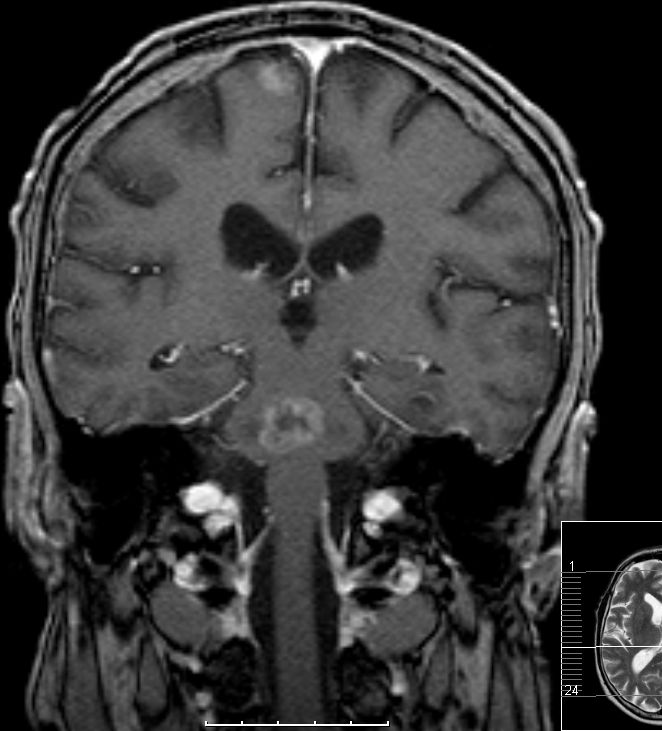

| MRT: multiple Hirnmetastasen | 70-jähriger Mann, der vor einem Jahr ein Adenokarzinom des rechten Lungenmittellappens hatte. MRT-Untersuchung des Hirns, T1-Sequenz mit Kontrastmittel. Klinisch keine Symptome! | |||

![]() |